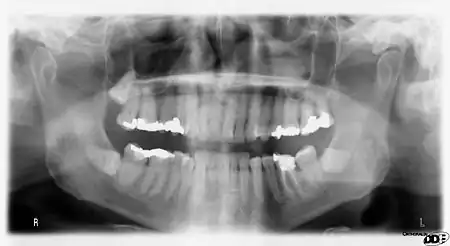

It is possible for both tooth decay and periodontal disease to be missed during a clinical exam, and radiographic evaluation of the dental and periodontal tissues is a critical segment of the comprehensive oral examination. The photographic montage at right depicts a situation in which extensive decay had been overlooked by a number of dentists prior to radiographic evaluation.

Panoramic films

Panoramic films are extraoral films, in which the film is exposed while outside the patient's mouth, and they were developed by the United States Army as a quick way to get an overall view of a soldier's oral health. Exposing eighteen films per soldier was very time consuming, and it was felt that a single panoramic film could speed up the process of examining and assessing the dental health of the soldiers; as soldiers with toothache were incapacitated from duty. It was later discovered that while panoramic films can prove very useful in detecting and localizing mandibular fractures and other pathologic entities of the mandible, they were not very good at assessing periodontal bone loss or tooth decay.[18]